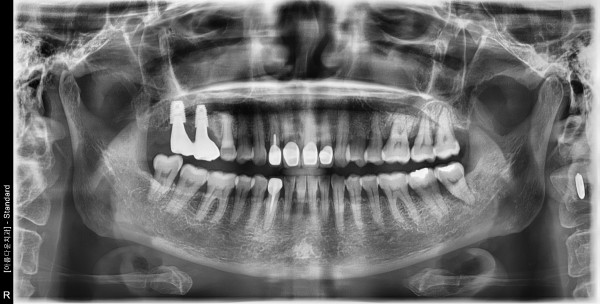

60세 여/ 상악 좌측 어금니 발치 및 치조골이식술 후 임플란트 식립